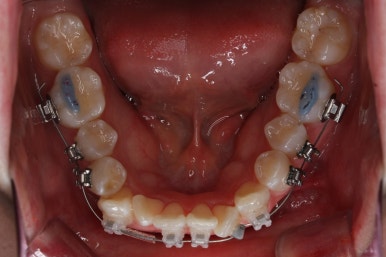

이 뽑은 자리가 점점 줄어드는 것이 보입니다.

아랫니도 많이 가지런해졌네요.

이 뽑은 자리가 반 이상 줄어든 것 같네요. 아랫니는 마무리를 해도 될 정도로 많이 좋아졌습니다.

이 쯤되면 중간평가를 하게 됩니다.

입 모양을 보고 얼마나 더 넣을지, 앞으로는 어떤 방향으로 치료하게 될 지 다시 한 번 점검하는 것이지요.

처음 보다는 입이 많이 들어갔습니다.

다만 아직 턱끝에 힘이 들어가는 것을 봐서 입을 더 넣어야 될 필요가 있어 보입니다.

입을 만힝 더 넣을 것 같으면 아랫니쪽에도 미니스크류를 식립해서 아래는 발치 없이 통째로 뒤로 밀어넣을 수 있겠습니다.

이 뽑은 틈은 거의 없어져가고 있고, 중간평가 이 후 더 필요한 위치에 미니스크류를 추가하여 당기고 밀고 밀어넣고 다양한 작업을 해주게 됩니다.